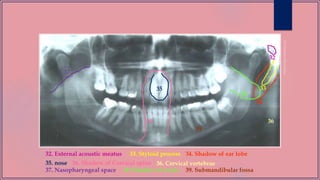

1. Condylar head 2. Sigmoid notch 3. Coronoid 4. External oblique ridge

5. Mandibular canal

2

3

4

5

6. Post. Border of Ramus 8. Lower border7. Gonial Angle

6

7

9. Mental ridge 11. Mental foramen10. Genial tubercle

13. Lingula

12. Internal Oblique Ridge

14. Hyoid bone

8

9

10

11

12

13

15

15. Glenoid fossa

19. Floor of Max.Sinus

17. Zygomatic Arch16. Articular eminence 18.Post. wall max. sinus

20. Zygomatic process of max. forming inominate line

21. Hard palate 22. Floor of the orbit 23. Nasal septum 24. Incisive foramen

25. Inferior choncha 26. Meatus 27. Frontal process of Z.bone

16

17

18

19

20

21

22

23

29

25

24

26

28.Pterygo max. fissure

30. Maxillary tuberosity29.Spine of the sphenoid bone 31. Lateral pterygoid plate

31

30

28

27

32

32. External acoustic meatus 34. Shadow of ear lobe33. Styloid process

35. nose 36. Shadow of Cervical spine

33

34

35

36 36

36. Cervical vertebrae

37

37. Nasopharyngeal space 38. Shadow of uvula

39

38

39. Submandibular fossa